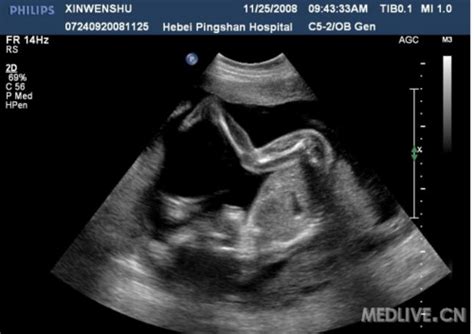

从您提供的数据来看,“孕30周,股骨长5.4cm,双径顶7.5cm”,

坯胎的发育不算明显的异常。

起码这个数据不能作为软骨发育不全的诊断依据。